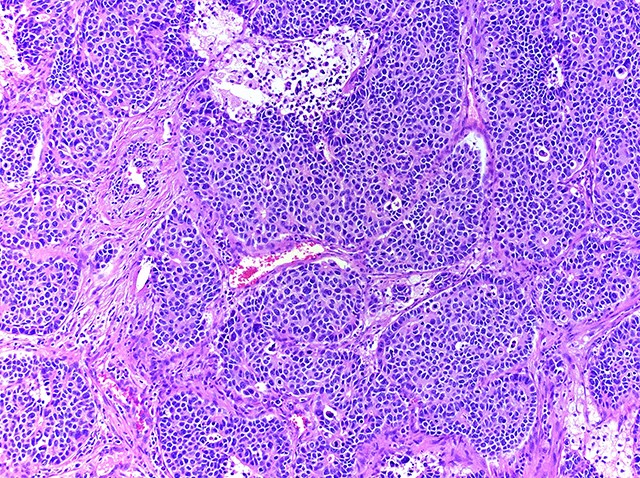

- Neuroendocrine organoid architecture may include nesting with peripheral palisading, anastomosing trabeculae and rosette-like structures (Mod Pathol 2022;35:36)

- > 10 mitoses/2 mm2, extensive / geographic necrosis

- Large cells (~3x size of small cell carcinoma) with abundant amphophilic cytoplasm, intercellular membranes, nuclear pleomorphism, variably coarse, granular or vesicular chromatin with prominent nucleoli (Transl Lung Cancer Res 2020;9:860, Mod Pathol 2022;35:36)

- Larger tumor cells than atypical carcinoid, high nuclear grade, increased mitotic activity and necrosis (Arch Pathol Lab Med 2010;134:1628)

Microscopic (histologic) images

Contributed by Ioanna Abba Nteka, M.D., Aggeliki Cheva, M.D., Ph.D., Antonia Loukousia, M.D., Roseann Wu, M.D., M.P.H. and Kyriakos Chatzopoulos, M.D., Ph.D.